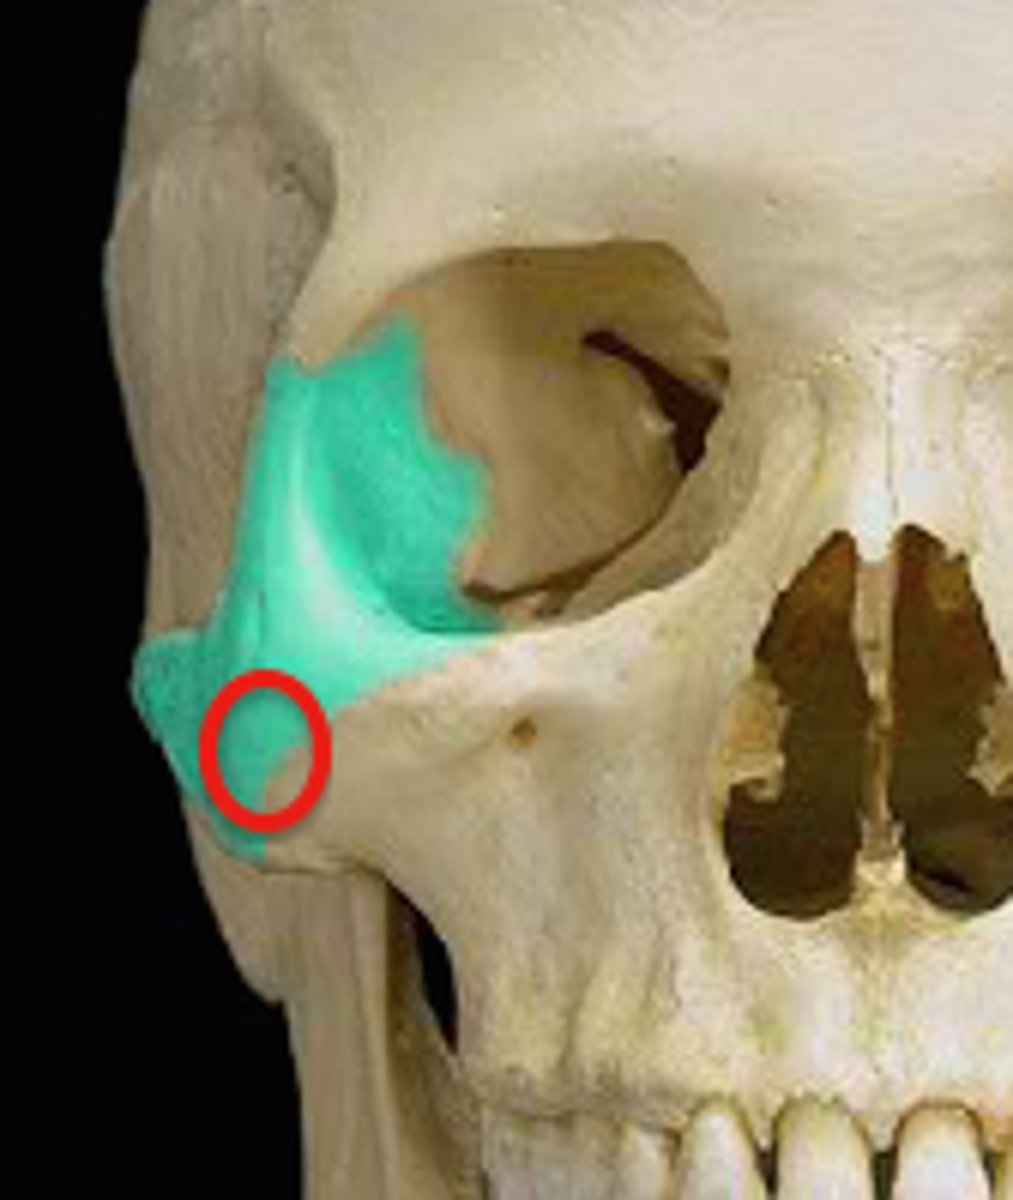

sphenoid bone

greater wing of sphenoid bone

posterior and inferior to lesser wing on the interior of the skull, also visible in the posterior orbit and lateral side of the skull

mandibular fossa of temporal bone

Articulates with the head (condoloid process) of the mandible to form the temporomandibular joint. The mandible (lower jaw) joins with the skull at this site.

zygomatic process of temporal bone

extension from the temporal bone that forms the posterior portion of the zygomatic arch, attachment point for temporal fascia

temporal process of zygomatic bone

short extension from the zygomatic bone that forms the anterior portion of the zygomatic arch

pterion

Junction of frontal, parietal, sphenoid, and temporal bones. Structural vulnerability as it is thin and middle meningeal artery is just deep, so hard head blow can result in subdural hematoma